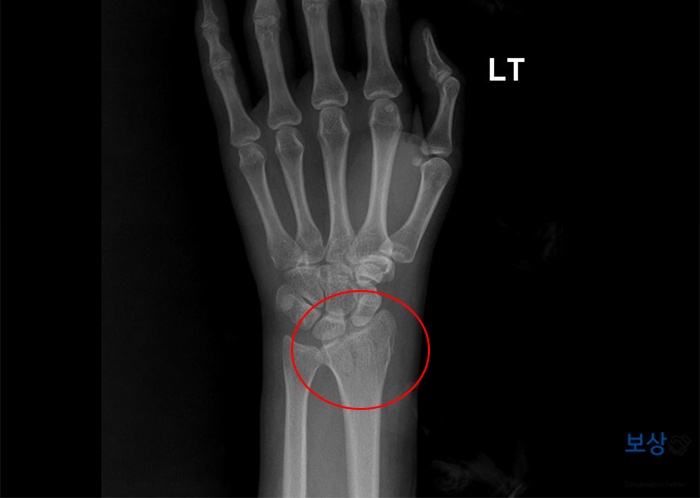

[주] 좌측 요골 하단의 상세불명 골절 (S52.59) [부] 좌측 손목 및 수근골 인대의 외상성 파열 의증 (S63.3) 이 사고로 환자분은 손목 부분의 뼈(요골, 수근골) 골절되셨는데요. 위 사진에는 잘 보이지 않지만 두꺼운 요골 뼈 안쪽으로 골절 면이 생기게 되었습니다.